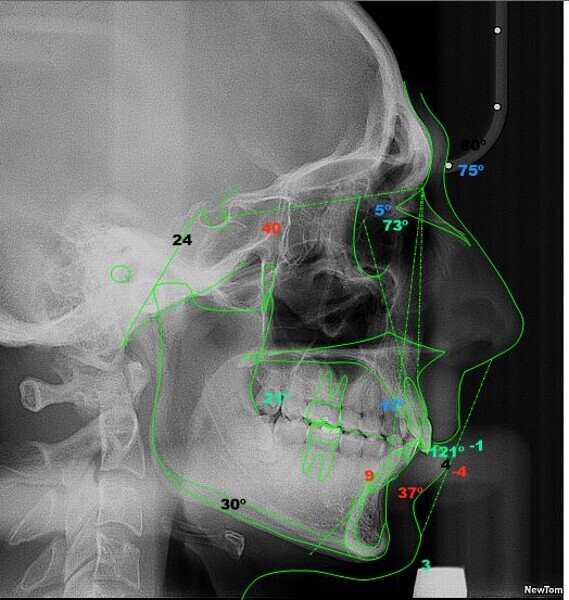

Four years after this case had been completed, the patient came for a review, and both radiographic and photographic records were taken to evaluate any changes that may have occurred over this retention period (Figs. 26–30). Cephalometric analysis was performed again and the results compared with the immediate post-treatment results (Table 2).

The radiographic equipment used on this occasion was not the same as we had used before, so the results obtained should not be considered totally accurate. Despite this setback, the patient’s status remained significantly better than at the beginning of treatment, since the patient still had a Class I occlusion, his profile was harmonious, and most notably, he was still satisfied with the results.

The pre- and post-treatment cephalometric tracings were also superimposed, obtaining the following results (Fig. 24):

• Area 1: Slightly closed facial axis due to mandibular antero-rotation, because of having placed a Class II CMA distaliser.

• Area 2: Molar distalisation as a result of the procedures that were used and protrusion of Point A due to the action of retroclining the central incisor.

• Area 3: Proclination of the mandibular incisor due to the Class II elastics.

• Area 4: Retroclination of the maxillary incisor.

• Area 5: Decreased lower lip protrusion.

Fig. 24: Superimposed tracings, black corresponding to the pretreatment tracing and red to the post-treatment tracing.